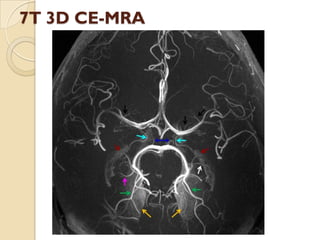

7T 3D CE-MRA

5- Yellow arrow demonstrate

stenosis of-

1- right ICA

2- right vertebral A.

3- right PCOM

4- Right MCA

9- Light blue arrow

demonstrate-

1- Anterior choroidal artery

2- Posterior choroidal

artery

3-PCOM

4- PCA

10- white arrow denotes-

1- Anterior choroidal